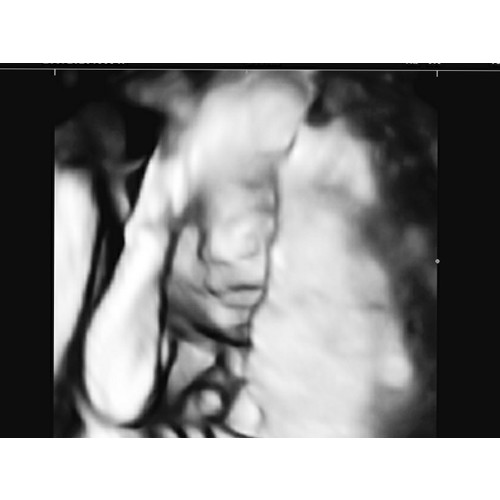

5 jaar geleden

En deze nog met haar voetjes voor gezicht. Iets minder scherp maar vind het erg schattig 🥰